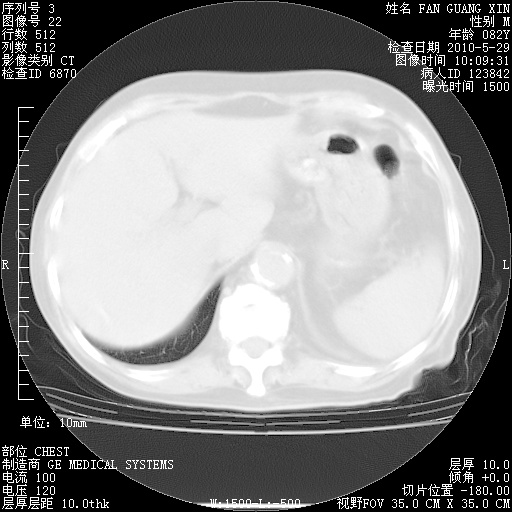

再治疗10天后的肺部CT 纵膈窗